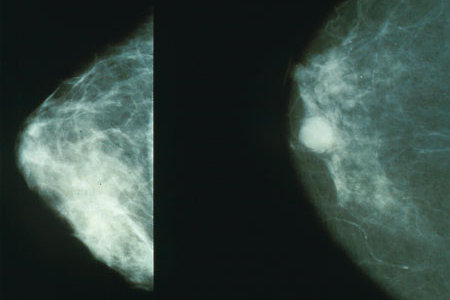

Zhoubné nádory prsu jsou u žen jedním z nejčastějších typů nádorového onemocnění. Ženám starším 40 let se proto jako prevence doporučuje každoroční vyšetření prsů na mamografu. Ženy z vysoce ohrožených skupin, které mají rodinné nebo genetické predispozice k rakovině prsu, ale s každoročním vyšetřováním začínají už ve věku kolem 30 let. Americká společnost pro výzkum rakoviny tuto praxi doporučuje, ale novější vědecké práce vyvolávají otázky, nakolik jsou mnohokrát opakované dávky měkkého rentgenového záření bezpečné.

Také výsledky nové studie holandských epidemiologů ukazují, že mamografie má i své stinné stránky. Vědci zjistili, že u mladých žen z vysoce rizikových skupin, které podstupují vyšetření na mamografu, je riziko vzniku rakoviny 1,5x větší než u těch, které které měkkému rentgenovému záření nebyly vystaveny. U žen, které na mamograf začaly chodit už před 20. rokem života, je riziko dokonce 2,5x větší. Autoři studie upozorňují, že tyto výsledky se týkají jen poměrně malé skupiny specificky ohrožených pacientek. Současně však v případech mladých žen doporučují zvážit také alternativní metody vyšetření, jako je ultrazvuk nebo magnetická rezonance.